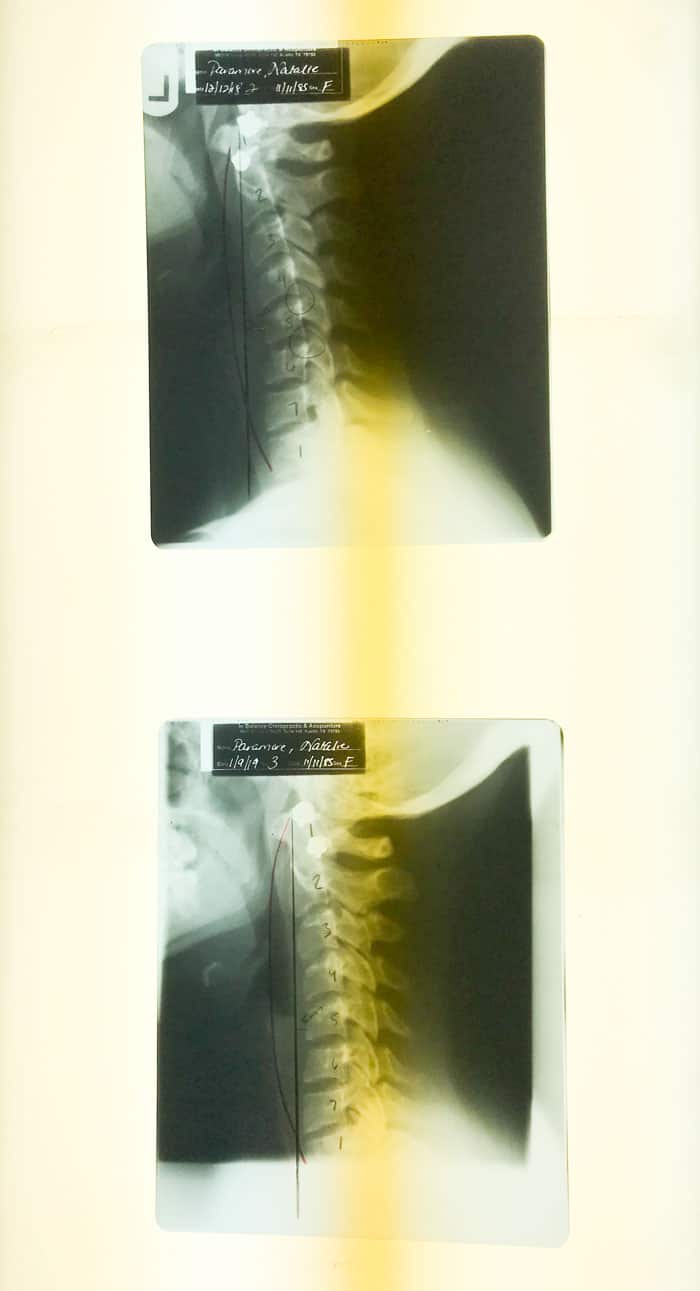

Top is my x-ray from my initial visit and bottom after one month. The dark, bowed line is the curvature of a healthy neck.

When the results came back, it validated that not only was my pain real, but that I had some serious stuff going on! I was diagnosed with mild scoliosis, TMJ and severe reverse curvature of the neck. The numbness in my arm was a sign of nerve damage because my neck was literally bowing out the opposite way that it is supposed to! How scary is that?!

My reverse curvature of the neck was most likely caused by car wreck I was in 10 years ago and then made worse by staring down at a phone or computer screen all day. Dr. De Luna says this condition is on the rise and is seeing lots of younger and younger people coming into her office with neck and shoulder pain due to staring down all day.

After the first month, we redid the tests and x-rays and they revealed that I had gained a lot of strength back in my arms and was able to lift more weight. My shoulders were also much more flexible! The scoliosis saw a 50% improvement in the curve in just one month! My legs were almost completely even too. The best news was the my neck curve saw an almost 50% improvement as well! We both couldn’t believe it! Usually necks can take a lot of time to heal. My neck is now straight, which is still a problem, so we are going to continue working on it but needless to say, we are seeing great results!